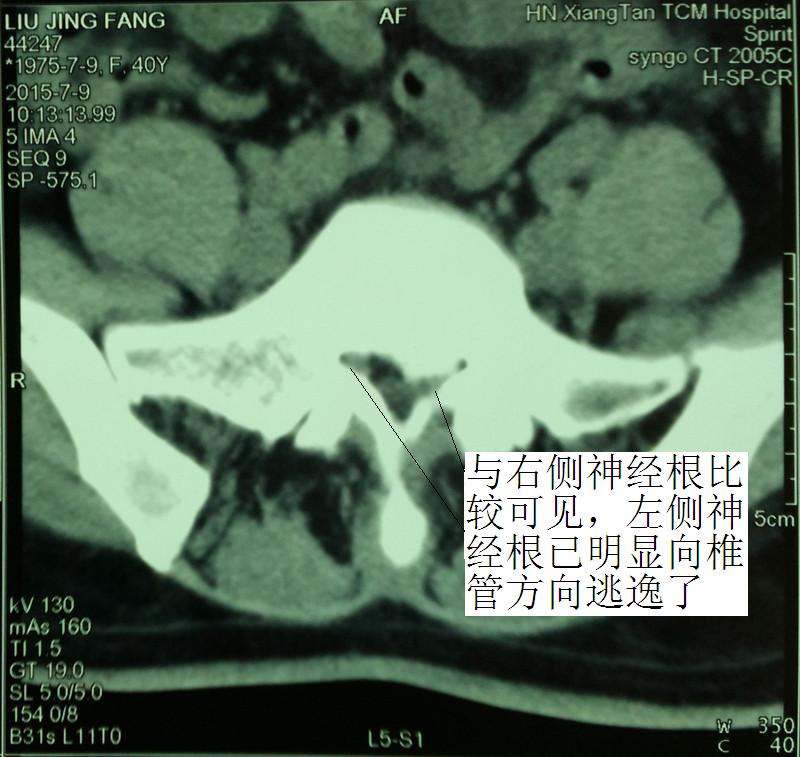

那疑問點來了:5年前的發(fā)作的L5/S1明顯突出,為什么近5年一直未復發(fā)呢?仔細閱片可知,L5/S1左側神經所在的側隱窩明顯狹窄,但神經根的位置已明顯向椎管方向移位了,這是典型的受壓神經根的自我逃逸!因為5年前的那次發(fā)病,受壓的神經根可謂處于水深火熱之中,但劇烈疼痛后,神經根變“聰明”了,顯然已從嚴重狹窄的側隱窩向椎管方向逃逸, 采取了“惹不起便躲起”的“走為上”之策。